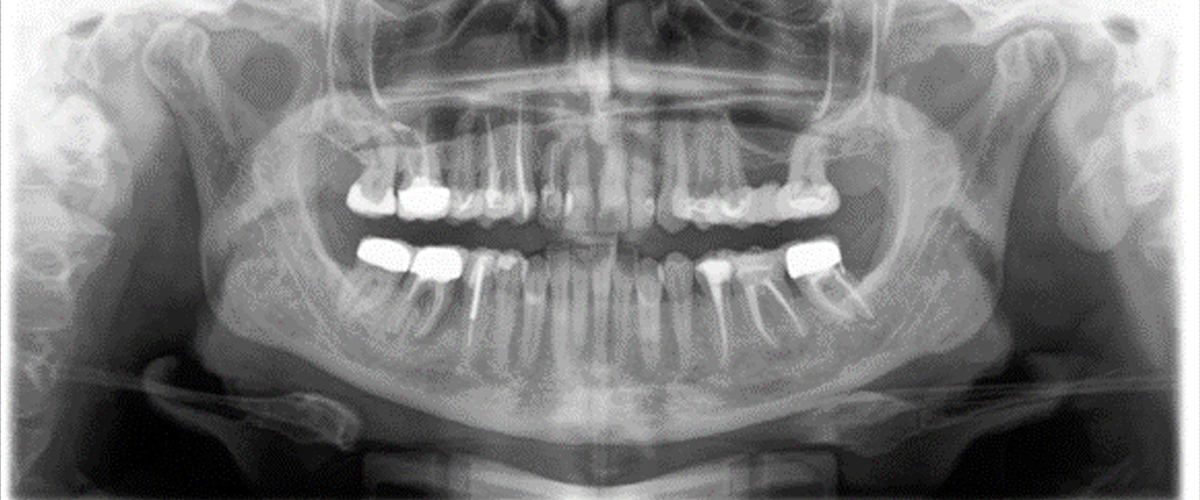

Cone beam computer topography (CBCT) is a similar technology used in hospital CT scanners. The technology has been refined to provide lower doses and more accurate images of your teeth and jaws. We have on site a state-of-the-art CBCT scanner, this can provide us with 2D and 3D images to enable us to diagnose your condition and plan the treatment. Imperative with implant treatment.

Our CBCT machine also has the capability to take extraoral bitewing radiographs. If you find standard intra oral x-rays too difficult to tolerate, some patients may find this an easier alternative.

Our intraoral x-rays are now all digital, reducing the dose whilst increasing the quality of the image, these have the big advantage they are instant and can be viewed with you at your consultation.